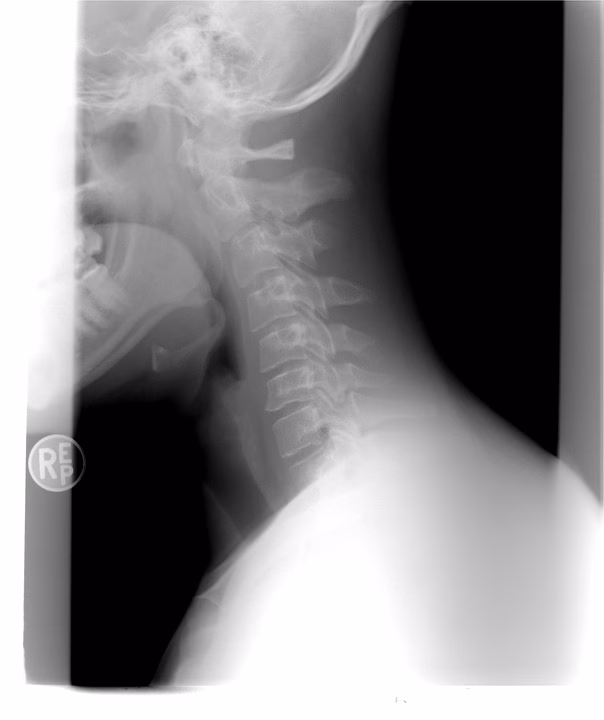

DeepSeek-Multimodal 2025 is an advanced AI model designed to revolutionize medical imaging diagnostics by integrating multiple data modalities—such as X-rays, MRIs, and CT scans—into a single, cohesive analysis system. Developed by DeepSeek AI, this model enhances diagnostic accuracy, reduces human error, and accelerates decision-making in healthcare. Its multimodal approach allows for cross-referencing different imaging techniques, leading to more precise disease detection and personalized treatment plans. For medical professionals and AI novices alike, this technology represents a significant leap forward in AI-assisted healthcare, improving patient outcomes while optimizing clinical workflows.

DeepSeek-Multimodal 2025 is an artificial intelligence model developed by DeepSeek AI, specializing in medical imaging diagnostics. Unlike traditional AI models that analyze one type of imaging data (e.g., only X-rays or MRIs), this system integrates multiple imaging modalities—such as X-rays, CT scans, ultrasounds, and MRIs—to provide a comprehensive diagnostic assessment. By cross-referencing different imaging techniques, the AI can detect anomalies with higher accuracy than single-modality systems.

The model leverages deep learning algorithms trained on vast datasets of annotated medical images. It uses convolutional neural networks (CNNs) for image recognition and transformer-based architectures for contextual understanding. When a radiologist uploads multiple scans of a patient, the AI synthesizes the data, identifies patterns, and flags potential abnormalities—such as tumors, fractures, or early signs of degenerative diseases—with remarkable precision.